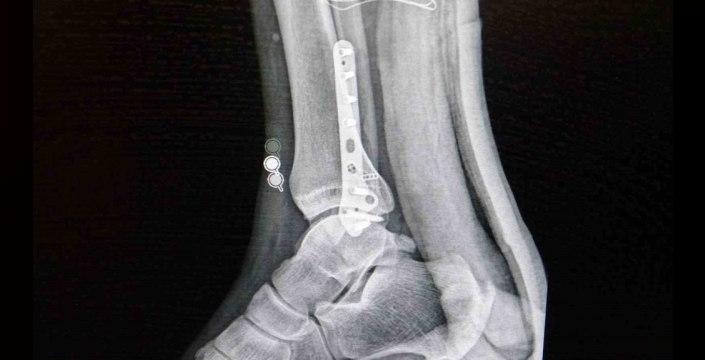

Ortopedi polikliniklerine en sık ayak bileği, diz ve omuz yaralanmaları ile başvurulduğunu belirten Op. Dr. Demirbaş, futbolun yaralanma oranlarında ilk sırada yer aldığını açıkladı. Futbolda menisküs yırtıkları, ön çapraz bağ yırtıkları, aşil tendon kopmaları ve çeşitli bağ yaralanmalarının çok sık görüldüğünü ifade etti.